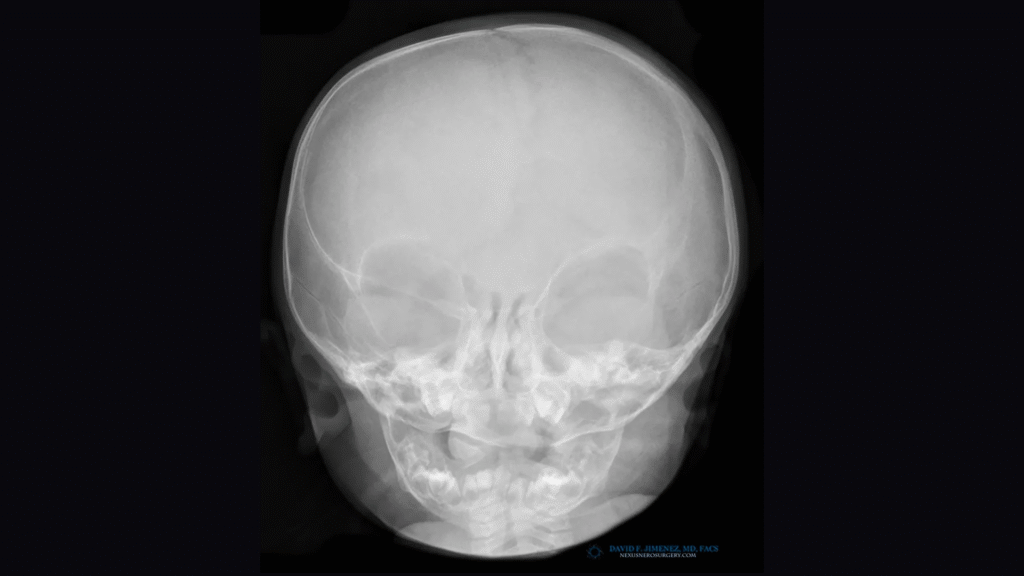

Endoscopic-assisted craniosynostosis surgery is a minimally invasive technique developed to treat infants diagnosed within the first few months of life. Introduced more than two decades ago, this approach allows for safe and early correction of abnormal skull growth by releasing the fused suture through small incisions.

The principle behind the endoscopic method is to use the natural, rapid growth of the infant brain to reshape the skull once the restriction is released. Because the incisions are small and the bone removal limited, this method reduces surgical time, blood loss, swelling, and hospital stay compared to open cranial vault reconstruction.